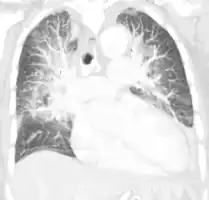

Acute pulmonary edema on CT

Pulmonary edema on CT-scan (coronal MPR)

Low oxygen saturation and disturbed arterial blood gas readings support the proposed diagnosis by suggesting a pulmonary shunt. A chest X-ray will show fluid in the alveolar walls, Kerley B lines, increased vascular shadowing in a classical batwing peri-hilum pattern, upper lobe diversion (increased blood flow to the superior parts of the lung), and possibly pleural effusions. In contrast, patchy alveolar infiltrates are more typically associated with noncardiogenic edema[8]